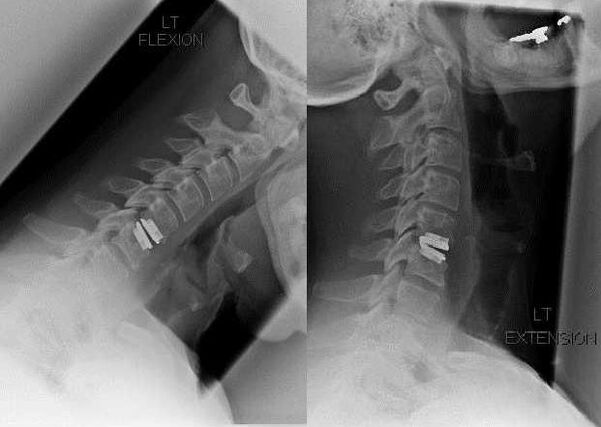

Χειρουργική επέμβαση

Οι ενδείξεις για χειρουργική επέμβαση περιλαμβάνουν την αναποτελεσματικότητα της συντηρητικής θεραπείας, καθώς και τις επιπλοκές της αυχενικής οστεοχόνδρωσης, για παράδειγμα, δισκογενή μυελοπάθεια, σύνδρομο σπονδυλικής αρτηρίας και ριζικό σύνδρομο. Για την αποσυμπίεση του νωτιαίου μυελού, των αιμοφόρων αγγείων και των ριζών της σπονδυλικής στήλης, εκτελούνται οι ακόλουθες επεμβάσεις:

Κατά τη διάρκεια της χειρουργικής επέμβασης, τα θραύσματα των οστών και οι σύνδεσμοι μπορεί να αφαιρεθούν και οι μεσοσπονδύλιοι δίσκοι να αφαιρεθούν πλήρως ή μερικώς. Για μικρές κηλικές προεξοχές, γίνεται συχνά εξάτμιση με λέιζερ του πυρήνα του δίσκου.

Μετά την εκτομή των σπονδυλικών δομών, συχνά απαιτείται σταθεροποίηση των τμημάτων κίνησης της σπονδυλικής στήλης με σπονδυλική σύντηξη ή εγκατάσταση οστικών και δερματικών αυτομοσχευμάτων.